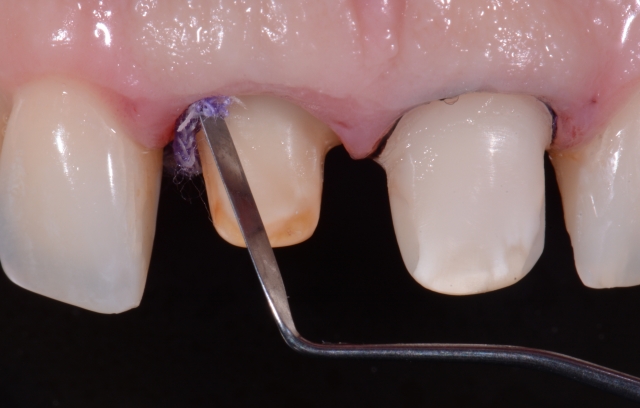

The first apically-located cord is generally a smaller diameter and will remain in place during the entire procedure. The purpose of the first cord is to retract the tissues in an apical direction and to block thin material remnants torn from the set impression from penetrating and remaining in the sulcus. It’s recommended to start rolling the first cord from the interproximal area where the sulcus depth is larger and the tissue (papilla versus free gingival margin) is stiffer, allowing the cord to be fixed more easily.

In most cases, the second superficial cord is impregnated with hemostatic/astringent solution and placed at the level of the finishing line so that its superficial part is always visible after insertion. This superficial cord is typically thicker than the first cord and aimed at laterally deflecting the gingiva and creating enough space for the impression material to capture the preparation margin.